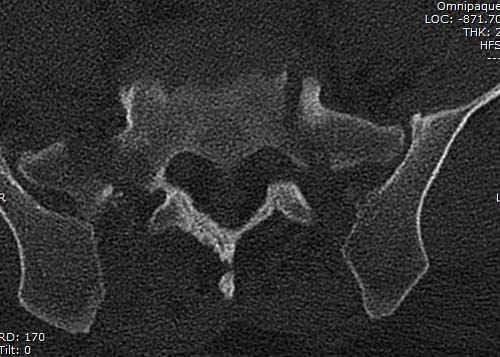

Двухстороннее повреждение крестца и травматическая ампутация бедра, где

неопытной бригадой дежурантов установлен верхний наружный фиксатор для

стабилизации. На третий день ревизия на более стабильный, и

окончательная фиксация. Первые снимки после стабилизации таза, и другие,

где показаны (параллельные) правильная установка на AIIS т.е на месте

прикрепления прямой мышцы бедра. Ампутация закончена костно пластическим

методом.